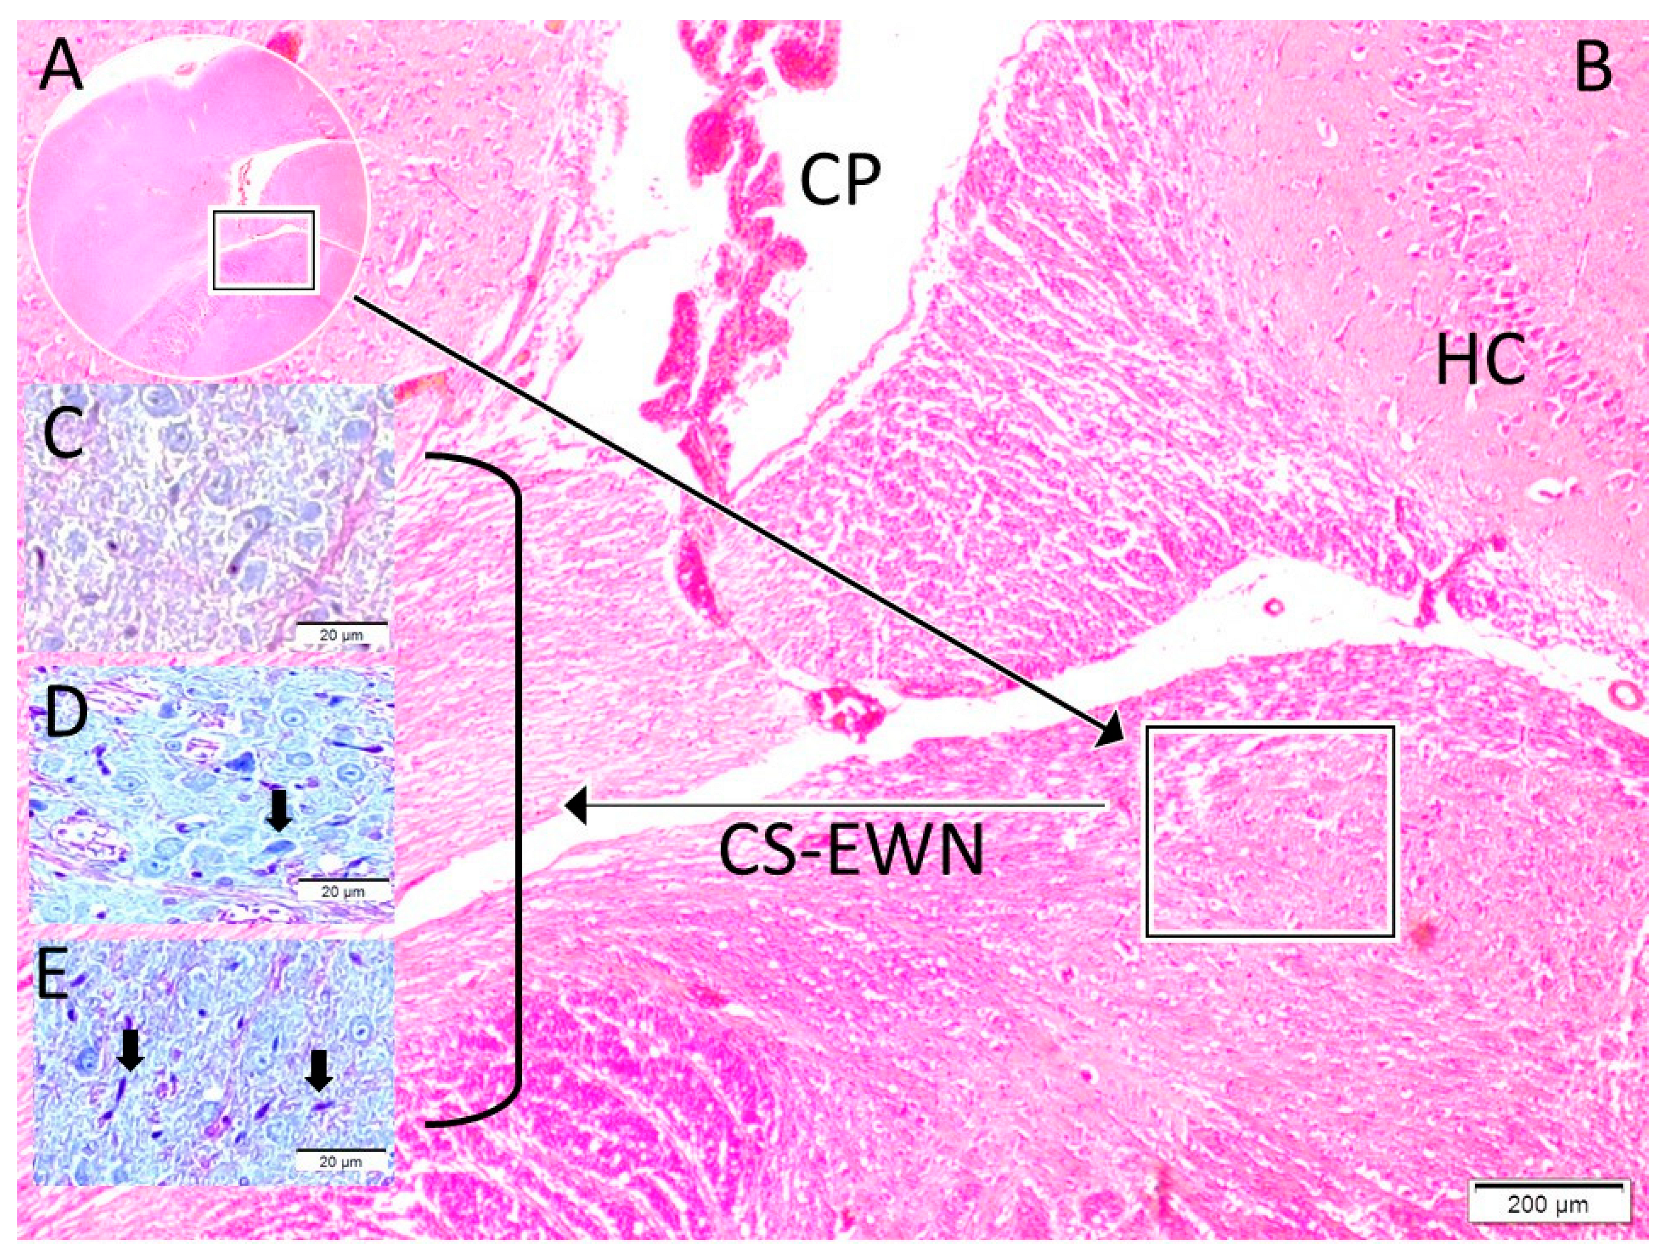

| Degeneration Neuron | Mean ± SS | 3.00 ± 0.95 | 12.00 ± 2.92 | 18.00 ± 4.00 | |||

| Median (Min–Max) | 3.00 (1.80–4.20) | 12.00 (8.20–15.80) | 18.00 (11.00–25.00) | 0.004 * | <0.001 * | 0.018 * |